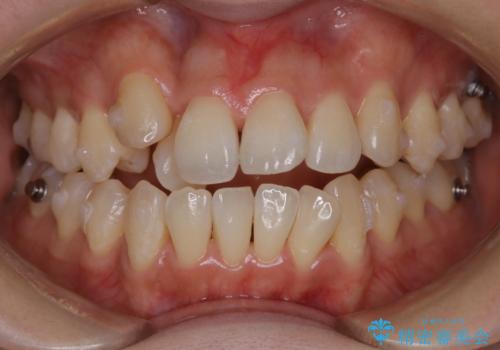

20代女性 ワイヤー矯正中にワイヤーを外してきれいにクリーニンング